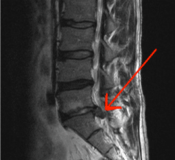

An MRI image showing a herniated disk Understanding the cause of low back pain is not simple. Often people will automatically assume that their problem has something to do with their disks, those shock-absorbing circles of cartilage wedged between each vertebra. [The MRI shown here is pointing to a herniated disk.] Mysteriously, the disks are rarely the problem! One back study looked at 99 people who were completely healthy and free of LBP. They were give MRIs and 2/3rds of these people showed structural problems with their disks, but felt no pain and had no disability. Conversely, there are many studies that show people with LBP have no structural problems at all with their spines. Even more confusingly, people who had apparent structural disk problems who had undergone spinal surgery still had LBP, even though subsequent investigations showed that the surgeries completely fixed the structural problem. The conclusion reached from the above observations is that – most low back pain is not caused by structural problems in the spine.[2]